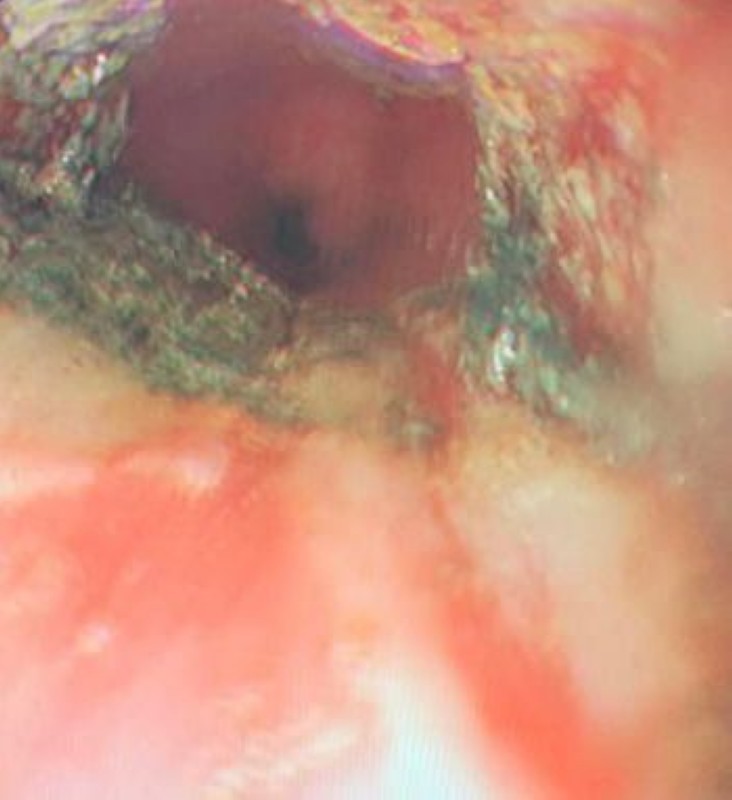

تمكن فريق طبي بمستشفى الولادة والأطفال بمكة المكرمة بقيادة استشاري الجهاز الهضمي الدكتور علي الشمراني من إنقاذ حياة طفلة غير سعودية تبلغ من العمر 4 سنوات ابتلعت بطارية حارقة. وتم نقل الطفلة إلى طوارئ المستشفى بعد مرور ١٢ ساعة على ابتلاعها للبطارية، حيث ذابت المادة الكيميائية حول البطارية ما أدى إلى حروق في منطقة المريء الوسطى في طبقتين على الأقل أحدثت نزفاً دموياً تمت السيطرة عليه، حيث تم التعامل مع النزف ونزع البطارية واستخراجها، وهي تخضع للعلاج الطبي بالمستشفى للاطمئنان على صحتها.